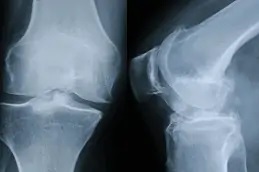

تُعد حقن البلازما الغنية بالصفائح الدموية (PRP) أحد الأساليب المستخدمة في علاج الركبة، حيث يُؤخذ مقدار صغير من دم المريض ويُعالج باستخدام جهاز الطرد المركزي لفصل مكونات الدم، واستخلاص البلازما والصفائح الدموية، بعد ذلك يُعاد حقن هذا التركيز مباشرة في الركبة أو المفصل المتضرر للمساعدة في تعزيز الشفاء.

| سحب الدم: | يتم أولاً سحب كمية صغيرة من دم المريض، غالبًا من منطقة الذراع. |

| الطرد المركزي: | يتم وضع الدم في جهاز طرد مركزي لفصل البلازما والصفائح الدموية عن باقي مكونات الدم. |

| الحقن: | يُملأ محلول PRP المستخلص في حقنة خاصة، ويقوم طبيب مختص بحقنها مباشرة في مفصل الركبة. |

| الاستجابة للعلاج: | تعمل عوامل النمو في حقن PRP على تقليل الالتهاب وتحفيز إصلاح الأنسجة المتضررة. |